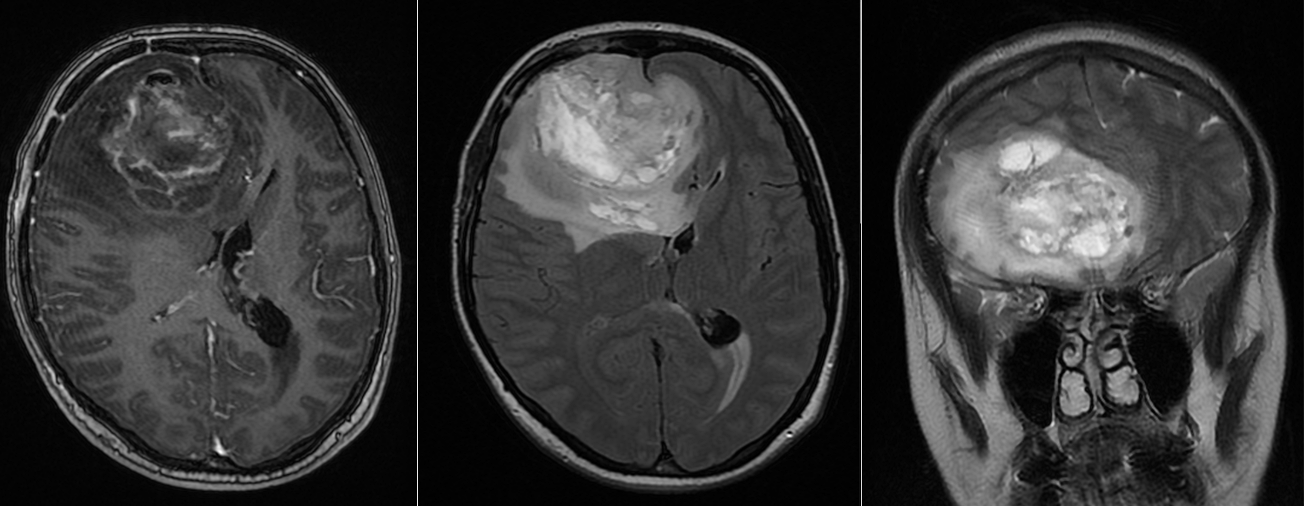

Se reface imagistica – de aceasta dată RMN cerebral cu contrast – și se constată prezența unei tumori cerebrale infiltrative de cca 7/7/6 cm, în cea mai mare parte negadolinofila, hipo-T1, hiper-T2 și FLAIR, cu zone hemoragice la interior și efect de masă important – deplasarea structurilor liniei mediene cu 2 cm, hernie de girus cinguli și hidrocefalie internă prin obstrucția formen Monro – imagine sugestivă pentru un gliom de grad înalt, cel mai probabil glioblastom.

La internarea în serviciul nostru, pacienta este în stare neurologică ușor alterată, somnolentă, confuză, GCS = 12-13, fără deficite neurologice focale, cu strabism divergent prin pareză de nerv abducens drept; mers posibil cu sprijin. Simptomatologia se ameliorează parțial la administrarea de Dexametazonă și Manitol.